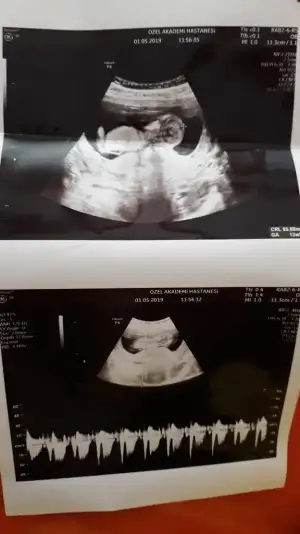

Kontrolden çıktık sata gore 12+4 ultrasona gore geriden gelen bebişim bugun 13+2 cikti :) boyu 6.5 cm olmuş ense ve burun kemiğine iyi dedi kac diye sorunca 1den kucuk merak etme sorun yok dedi doktorum;) kan verdim 1 hafta sonra çıkacakmış sonuç doktorum cinsiyetle ilgili de kıza benziyor ama kesin değil dedi ve ben basından beri kiz hissediyorum:) en son gittiğimde mercimek tanesi kadardı ama bugun gercekten bir bebek gordum zıplayan kayan ellerini oynatan, Rabbimin gerçekten bir mucizesi Allahım hepimize boyle guzel haberler almayi nasip etsin inşallah tekrar :) 15567063923235918574424562188093.webp 15567064171896032461299685616764.webp

Kontrolden çıktık sata gore 12+4 ultrasona gore geriden gelen bebişim bugun 13+2 cikti :) boyu 6.5 cm olmuş ense ve burun kemiğine iyi dedi kac diye sorunca 1den kucuk merak etme sorun yok dedi doktorum:KK66: kan verdim 1 hafta sonra çıkacakmış sonuç doktorum cinsiyetle ilgili de kıza benziyor ama kesin değil dedi ve ben basından beri kiz hissediyorum:) en son gittiğimde mercimek tanesi kadardı ama bugun gercekten bir bebek gordum zıplayan kayan ellerini oynatan, Rabbimin gerçekten bir mucizesi Allahım hepimize boyle guzel haberler almayi nasip etsin inşallah tekrar :)Eki Görüntüle 2264270 Eki Görüntüle 2264272 Eki Görüntüle 2264270 Eki Görüntüle 2264272